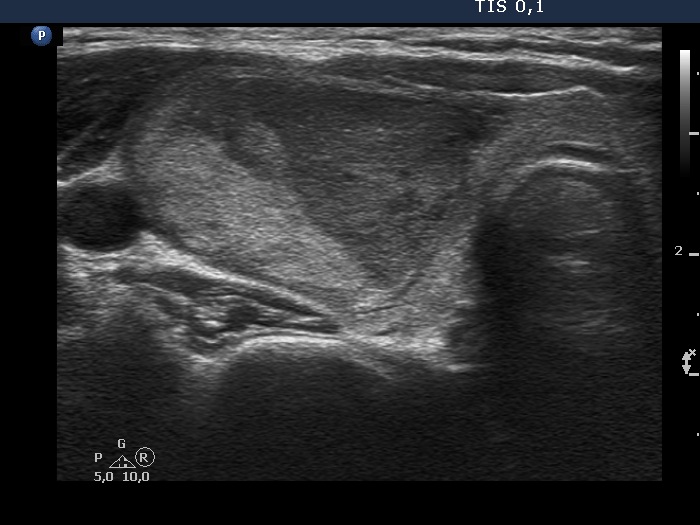

Ultrasonography. The thyroid was echonormal. There was a heterogeneous nodule in the right lobe. The lesion contained roughly equal proportions of echonormal and moderately hypoechoic portions. The nodule had a thin halo and presented perinodular blood flow.